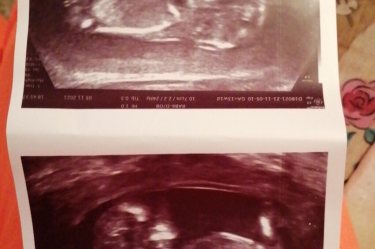

Всем привет! Вчера прошла первый скрининг! Жду результата анализа теперь, а по узи тьфу тьфу тьфу сказали всё хорошо! Такой уже большой🥰Как у вас прошёл первый скрининг?

13 недель 4дня на момент узи)